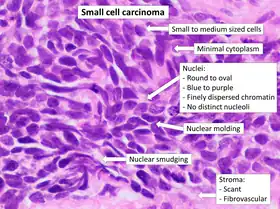

- Small cell carcinoma

- Cells are usually round and are less than approximately 3 times the diameter of a resting lymphocyte and with little evident cytoplasm. Occasionally, small cell malignancies may themselves have significant components of slightly polygonal and/or spindle-shaped cells.[8]